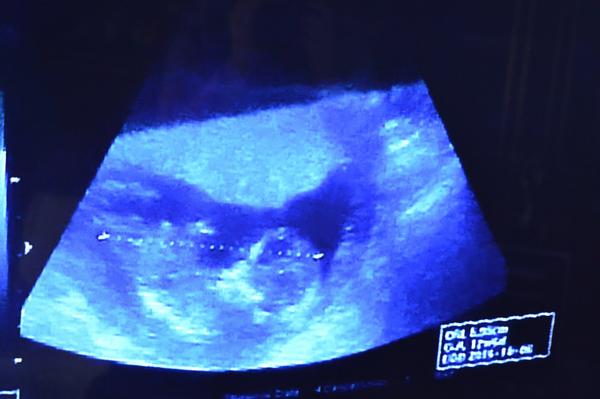

Dnes jsem byla po 4 týdnech na kontrole. Hlavička měřila 2,41cm (13+0) a tělíčko při prvním měření 6,13cm (13+0) a když měřil znova aby vytiskl fotečku tak jen 5,95cm (12+6) . Není to málo ? Všude se píše,že by měl mít tak 8cm

Přikládám foto z ultrazvuku před 4 týdny + dnešní + fota focené dnes mobilem z monitoru.